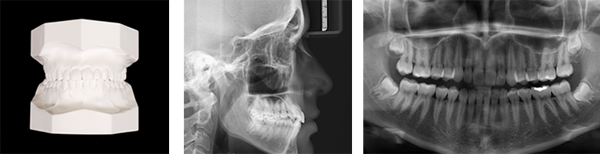

Documentação Ortodôntica

É uma série de exames incluindo radiografias, fotografias e modelos, utilizados para diagnóstico e planejamento do tratamento das má-oclusões dentárias e desarmonias dos ossos da face. Existem diversos tipos de documentações, podendo diferenciar de acordo com a necessidade de cada caso.

Modelo de Gesso

É uma replica em gesso das arcadas dentárias.

Modelo Digital

É uma replica digitalizada das arcadas dentárias.